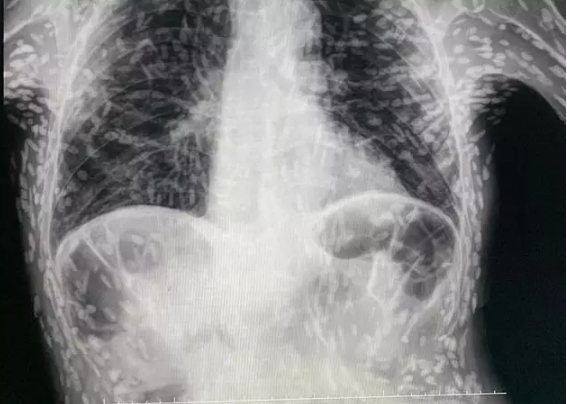

Ein Patient, der sich mit einem vermeintlich hartnäckigen Husten ins Krankenhaus begab, erlebte einen großen Schock, als sich herausstellte, dass der Grund dafür Dutzende von Bandwürmern waren. Dr. Vitor Borin P. de Souza, Arzt am Hospital das Clínicas Botucatu in São Paulo, Brasilien, teilte auf Twitter ein erschreckendes Röntgenbild des Fundes.

Twitter/Vitor Borin de Souza

© Twitter/Vitor Borin de Souza

Jeder der weißen Punkte auf dem erschreckenden Röntgenbild stellt eine Zyste und die verkalkten Überreste eines Parasiten dar. Er erklärte, dass bei dem Patienten eine MRT-Untersuchung durchgeführt wurde, um die Lage einer Zyste im Gehirn festzustellen, die häufig Kopfschmerzen und Krampfanfälle verursacht, aber auch zu Verwirrung, Schwindel, Infektionen, Sehstörungen und Hydrocephalus (übermäßige Flüssigkeitsansammlung im Gehirn) führen kann.